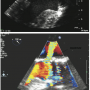

Periprocedural TEE showed the defect between the LV and the LA measured 7 mm (Figures 1A and B) and 2 color flow jets were visualized suggesting 2 leaks adjacent to each other. The defect was also clearly visualized on 3D TEE (Figure 2). TEE guidance is very useful in this situation to assess the anatomy clearly and guide device closure percutaneously.